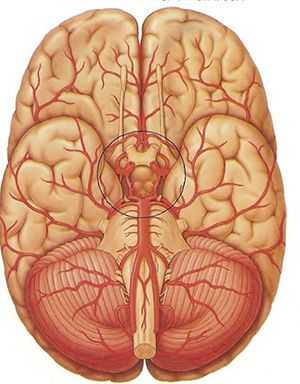

Общие сведения о базальном кровообращении, его сосудистой структуре и её функциях

Виллизиев круг является самым началом всей кровеносной сети, поднимающейся от основания головного мозга вверх как по его поверхности, так и в недрах, чтобы далее, бесконечно ветвясь, достигнуть каждой отдельной клетки в его тканях и структурах.

Замкнутая в кольцо артериальная система позволяет осуществлять свою основную функцию (бесперебойное снабжение мозга кровью) как нельзя более успешно, ибо при появлении перебоев с питанием из одного сосуда происходит автоматическое переключение на кровоснабжение из другого.

О строении этой части кровеносной системы

Существует множество вариантов построения артериального кольца основания мозга, но обязательными его компонентами являются артерии:

- передняя мозговая (её начальный фрагмент);

- задняя мозговая (на её начальном отрезке);

- соединительные (передняя и задние);

- внутренняя сонная (надклиновидный её фрагмент).

Основными сосудистыми магистралями являются 2 сонных и 2 позвоночных артерии (по одной с каждой стороны тела). Сонные входят в полость черепа посредством сонного канала, проходящего в пирамиде височной кости и открывающегося на её верхушке, позвоночные - миновав большое затылочное отверстие.